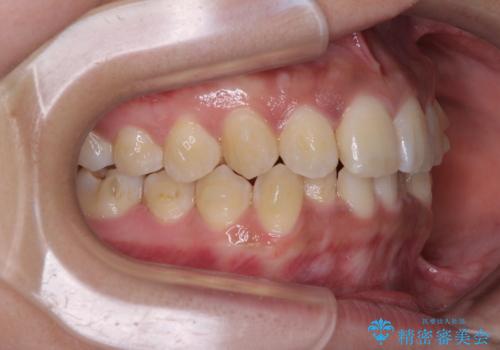

前歯のデコボコと隠れてしまう下顎前歯 インビザラインですっきりと改善

インビザライン発注後に長期滞在先から2年間ほど帰国することができず、インビザラインの有効期限内に終了できるのか不安でしたが、矯正治療開始後は十分な装着時間を達成され、1年未満の期間で無事に終えることができました。